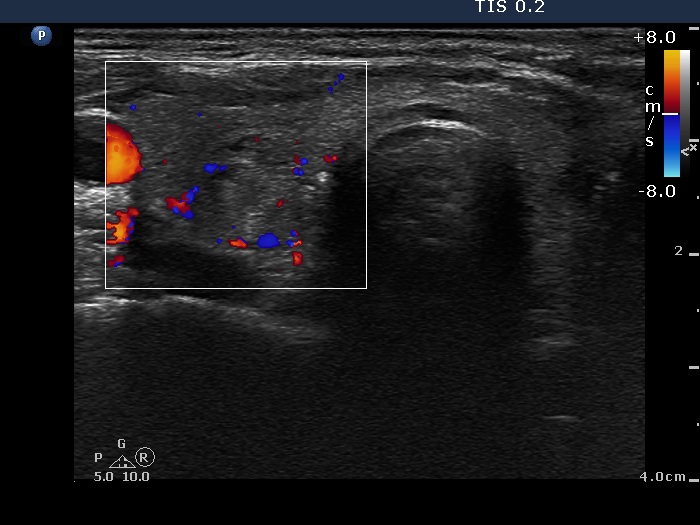

Ultrasonography: The right thyroid was echonormal and contained several small, insignificant lesions. There was a hypoechogenic lesion with blurred borders in the central and in the ventro-medial part of the left thyroid with increased intranodular blood flow.

The ultrasound pattern of de Quervain's thyroiditis and that of papillary cancer are very similar: a hypoechogenic lesion with blurred borders are found in both cases. They differ in vascularization statistically but the vascular pattern has only limited practical significance. In the acute phase of de Quervain's thyroiditis the vascularization is generally decreased but even in this case the situation was the opposite. The finding of not one but multiple hypoechogenic areas favored the possibility of subacute thyroiditis.